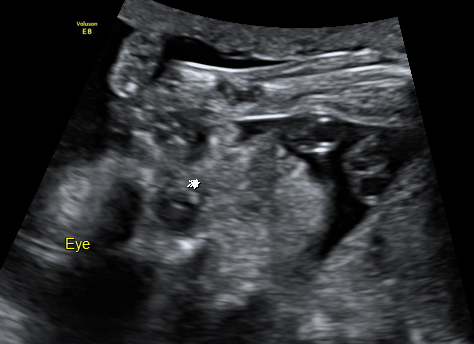

孕日記22w3d 自費高層次超音波 小芋圓心臟的小白點